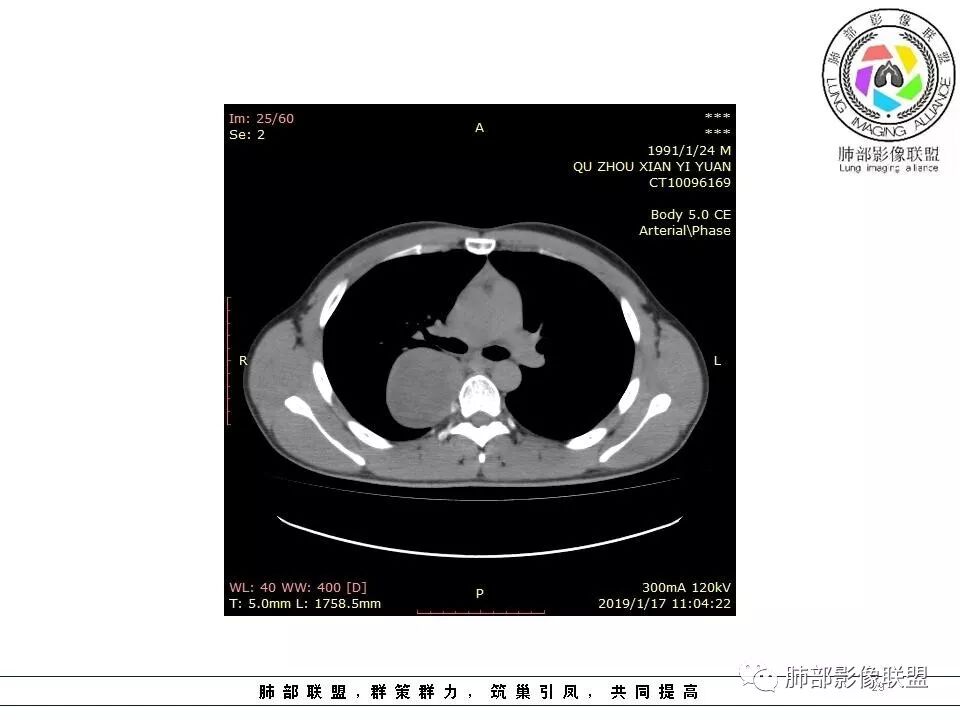

右后纵膈脊柱旁软组织占位,形态规则类圆,边缘光整,肺组织受压,胸膜尾,肋间动脉供血。中度不均匀延迟强化。

右后纵膈脊柱旁软组织占位,边界清晰,光整,肺组织受压。胸膜被掀起,肋间动脉供血,中度不均匀延迟强化。考虑神经鞘瘤,不除外纤维瘤

右后纵膈脊柱旁软组织影,与纵隔结构分界不清,形态规则类圆,边缘光整,肺组织受压,胸膜尾,肋间动脉供血。肺动脉推移,中度不均匀延迟强化。考虑神经来源,神经鞘瘤,神经纤维瘤二者不易鉴别。

青年男性,间断胸痛;右侧脊柱旁可见一类圆形软组织密度影,密度欠均匀,增强扫描呈轻中度持续强化,邻近肺组织及肺动脉推移,可见肋间动脉供血,部分胸膜下脂肪可见,部分层面似见与右侧椎间孔相连。考虑后纵隔神经源性肿瘤。

1.右上胸内脊柱旁类圆形肿块,质地似乎比较坚实,密度稍显不均,但未显示明确的坏死。

如此密度形态的病灶位于肺边缘首先应当想到孤立性纤维瘤,可相邻胸膜未见明显的异常强化和胸膜方向延伸。

2.肋间动脉病供血也提示肿块来自后纵隔?